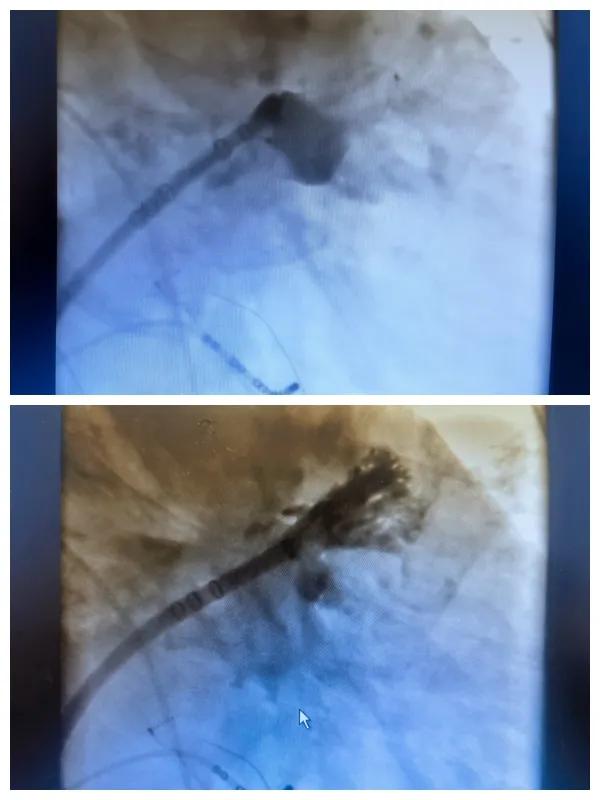

6月26日,市二院成功為一名老年房顫患者實(shí)施了房顫射頻消融術(shù)+左心耳封堵WM FLX一站式介入治療,標(biāo)志著醫(yī)院在心律失常介入治療領(lǐng)域邁出了嶄新的一步,開啟了新的治療篇章。

為了讓患者得到全面、綜合的治療,經(jīng)過(guò)團(tuán)隊(duì)術(shù)前充分討論,并征得家屬同意,心血管內(nèi)科團(tuán)隊(duì)決定采用目前國(guó)內(nèi)外先進(jìn)的房顫射頻消融術(shù)+左心耳封堵WM FLX一站式介入微創(chuàng)手術(shù)來(lái)治療老人的疾病。整個(gè)手術(shù)過(guò)程圓滿順利,術(shù)后何大爺各項(xiàng)體征正常,蘇醒后順利返回病房。